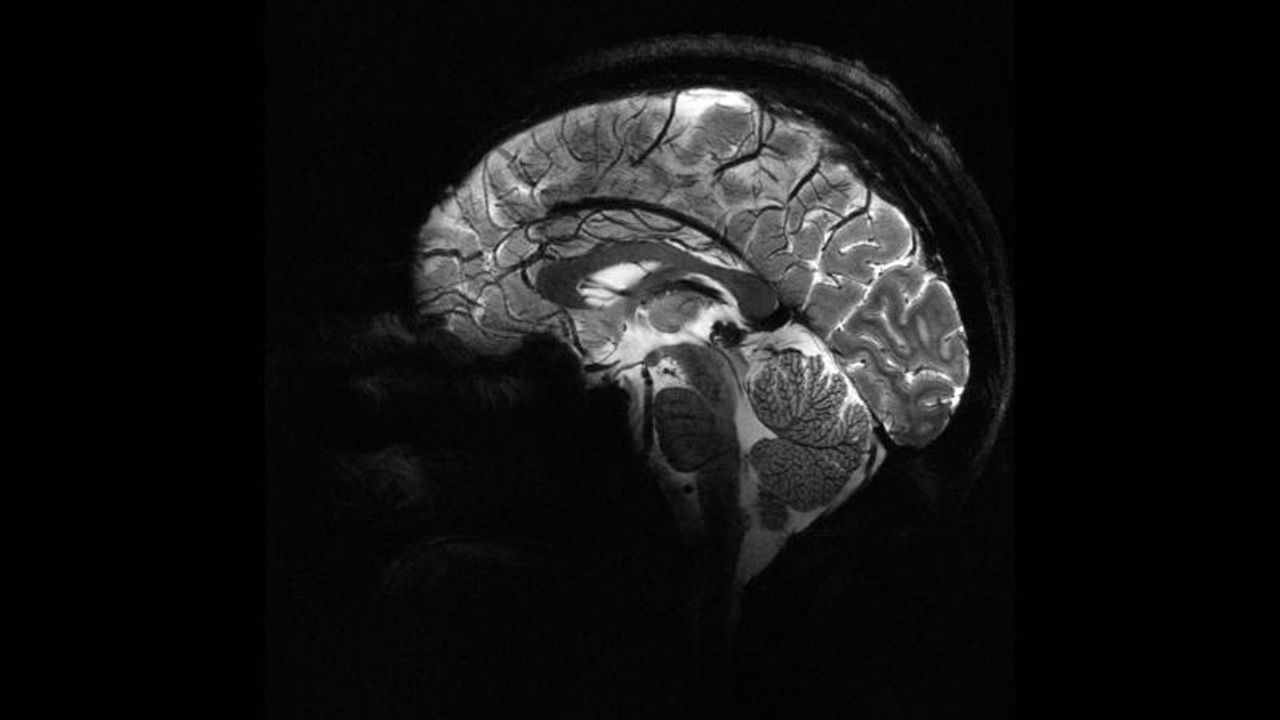

Beynin iki bölgesi aynı anda uyarıldı

Zürih Üniversitesi bünyesinde gerçekleştirilen çalışmada 44 gönüllüden, kendileri ile anonim bir kişi arasında belirli miktardaki parayı paylaşmaları istendi. Deney sırasında beynin frontal ve paryetal bölgelerine elektrik akımı uygulandı.

Bu iki bölgenin eş zamanlı uyarılması halinde katılımcıların daha fazla para paylaştığı gözlemlendi. Çalışmayı yürüten Prof. Christian Ruff, etkinin sınırlı ancak istatistiksel olarak anlamlı olduğunu ve paylaşma eğiliminde tutarlı bir artış görüldüğünü ifade etti.